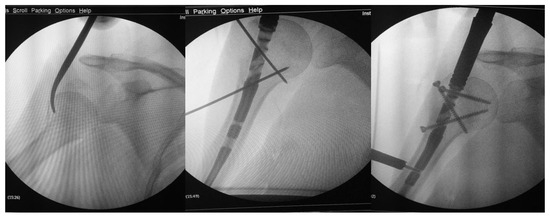

Figure 2. Intraoperative images. Surgery was performed through a percutaneous reduction and a minimally invasive nailing.

All procedures were performed by experienced orthopedic surgeons specialized in upper limb trauma surgery. Preoperative assessment included clinical examination and radiographic evaluation with standard anteroposterior and axillary views. In selected complex cases, CT scans were used to improve surgical planning and to confirm fracture classification. The operative technique was performed under general anesthesia or interscalene block. In the plate group, all procedures were carried out through a minimally invasive transdeltoid approach, which provided direct lateral exposure of the proximal humerus and allowed for accurate reduction and plate positioning under fluoroscopic control. In the nail group, fixation was achieved through a small (approximately 2 cm) anterolateral skin incision, followed by a limited incision of the supraspinatus tendon along the direction of its fibers to reach the nail entry point. The rotator cuff was systematically repaired at the end of the procedure using nonabsorbable sutures. Both surgical techniques aimed to achieve anatomical reduction and stable fixation, permitting early postoperative mobilization and functional rehabilitation.